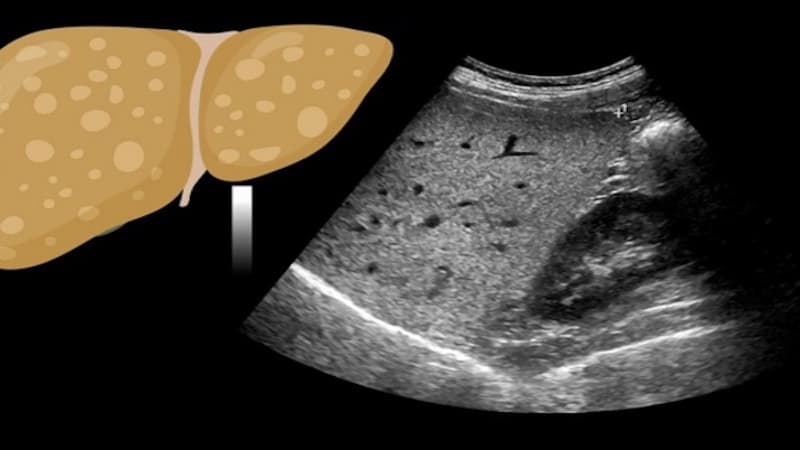

Bệnh gan nhiễm mỡ xảy ra khi lượng chất béo tích tụ quá nhiều trong gan, lâu dần có thể gây viêm và ảnh hưởng đến chức năng gan. Ở giai đoạn đầu, bệnh thường chưa gây ảnh hưởng nghiêm trọng đến sức khỏe. Tuy nhiên, nếu được phát hiện sớm, gan vẫn có khả năng cải thiện chức năng và phục hồi tốt. Vì vậy, nhiều người thắc mắc kiểm tra gan nhiễm mỡ bằng cách nào để phát hiện bệnh sớm.

Vậy xét nghiệm gì để biết gan nhiễm mỡ? Đó là xét nghiệm máu giúp đánh giá chỉ số men gan, chức năng gan, công thức máu toàn phần, hàm lượng sắt và phát hiện viêm gan virus mạn tính.